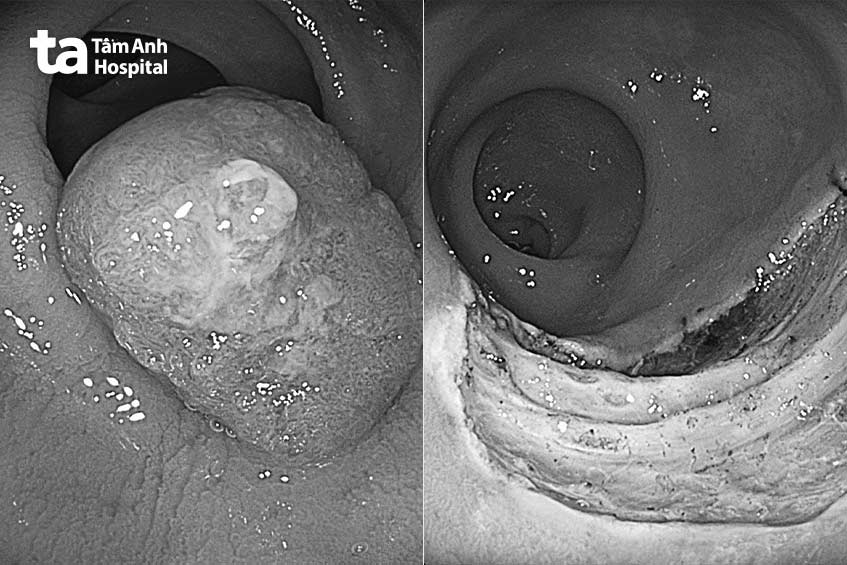

Như chị Xuân, 38 tuổi, ngụ Bình Dương, đi khám do hay đi tiêu ra nhầy máu. Kết quả soi đại trực tràng cho thấy một polyp lớn, kích thước 4 cm, lan rộng sang bên, hình thái bất thường bề mặt. Nghi ngờ polyp ung thư hóa giai đoạn sớm, bác sĩ Bình cho người bệnh lấy mẫu sinh thiết.

Kết quả sinh thiết cho thấy nghịch sản nhẹ, có vài vị trí nghi nghịch sản cao (dấu hiệu tiền ung thư). Người bệnh cũng được cắt polyp bằng phương pháp cắt tách dưới niêm mạc để lấy trọn khối polyp có kích thước lớn. Giải phẫu bệnh ghi nhận ung thư giai đoạn sớm trên nền u tuyến ống nghịch sản độ cao, chưa xâm lấn mạch máu, bạch huyết, bờ cắt an toàn. Sau nội soi, bệnh nhân tỉnh táo, không cần phải nhập viện.

Tương tự chị Nhân, 31 tuổi và anh Dương, 28 tuổi đi khám do rối loạn tiêu hóa. Kết quả nội soi đại tràng cho thấy trong đại tràng chị Nhân có nhiều polyp, khối polyp lớn nhất kích thước 2,5 cm ở trực tràng. Còn anh Dương được phát hiện polyp 4 cm qua phương pháp nội soi tương tự.

Theo bác sĩ Bình, nội soi nhuộm màu và phóng đại polyp của cả hai người bệnh đều có thay đổi cấu trúc bề mặt và mạch máu. Sinh thiết cho thấy polyp có nghịch sản độ cao nên họ có khả năng mắc ung thư trong thời gian tới.

Bác sĩ chỉ định cho họ cắt polyp bằng phương pháp cắt tách dưới niêm mạc (Endoscopic Submucosal Dissection – ESD) trong lúc nội soi đại trực tràng. Kết quả giải phẫu bệnh sau cắt polyp đều là ung thư giai đoạn sớm.